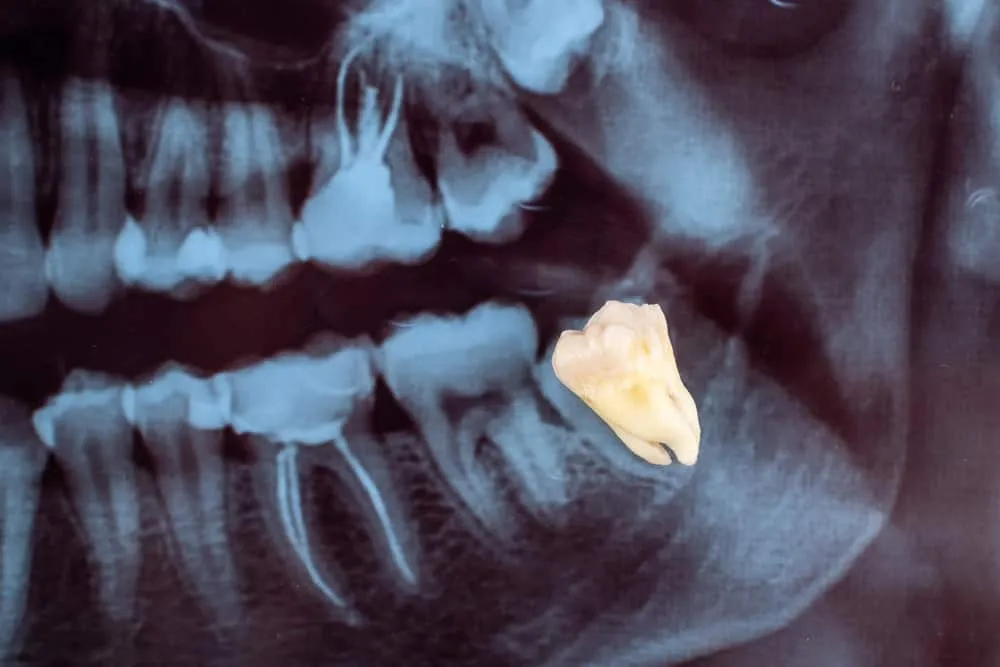

Răng hàm chính là những chiếc răng khỏe nhất trong miệng và là những chiếc răng mọc cuối cùng. Người trưởng thành có bộ răng hàm bao gồm 3 răng là răng số 6, 7, 8 và những chiếc răng nhỏ hơn được gọi là răng tiền hàm. Theo Hiệp hội Nha khoa Hoa Kỳ, những chiếc răng hàm đầu tiên thường xuất hiện vào khoảng 6 – 7 tuổi. Răng hàm thứ hai ở mỗi bên thường xuất hiện trong khoảng 11 đến 13 tuổi. Các răng hàm thứ 3 được gọi là răng khôn và xuất hiện khoảng từ 18 tuổi trở đi.

Trong khi răng nanh và răng cửa có vai trò cắn và xé thức ăn thành nhiều mảnh, thì răng hàm số 6 và số 7 lại đóng vai trò nhai và nghiền nát thức ăn trước khi nuốt. Chúng thường có kích thước lớn và bề mặt rộng, có nhiều góc nhọn và thường là các răng làm việc nhiều nhất.

Quy trình nhổ bỏ răng hàm diễn ra tùy vào vị trí răng hàm cần nhổ và tình trạng của răng. Đặc biệt là đối với răng khôn mọc lệch và răng khôn mọc ngầm, quy trình nhổ răng sẽ phức tạp và khó khăn hơn.